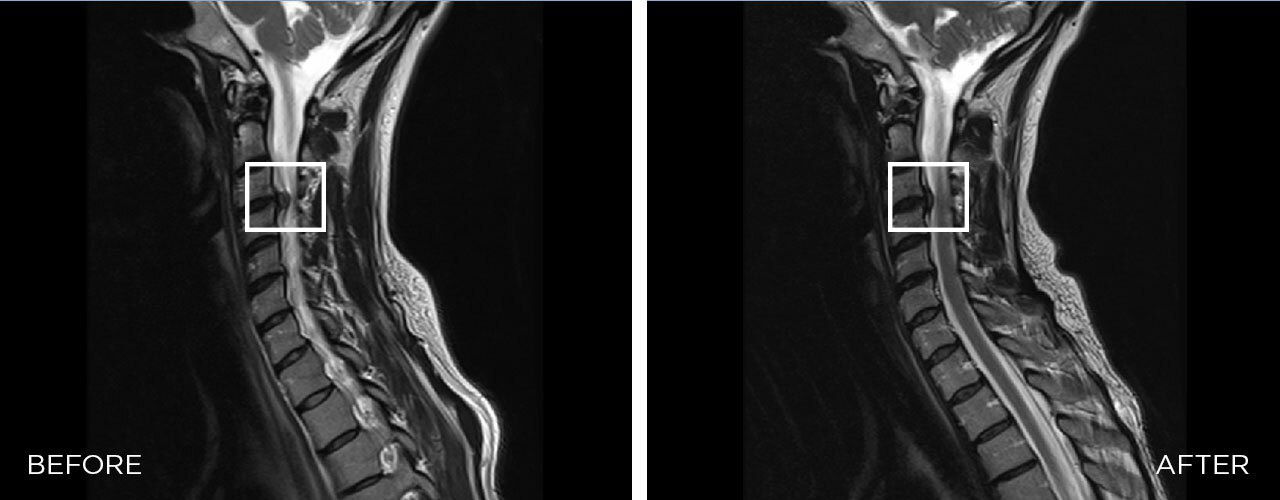

EFFICACY OF SPINAL DECOMPRESSION THERAPY IN INDIVIDUALS WITH CERVICAL DISC HERNIATION – A RANDOMIZED CONTROLLED TRIAL

The BTL SPINAL DECOMPRESSION is a mechanical therapy that uses automated decompressive forces to mobilize joints, relieve the pressure over neuro-spinal structures, and relax and elongate soft tissues.

The therapy is based on the targeting decompressive forces applied over vertebrae. Decompressive forces occur as automated and controlled cycles which leads to enlargement of intradiscal spaces, enhanced blood perfusion, disc rehydration, and realignment of vertebrae.Â